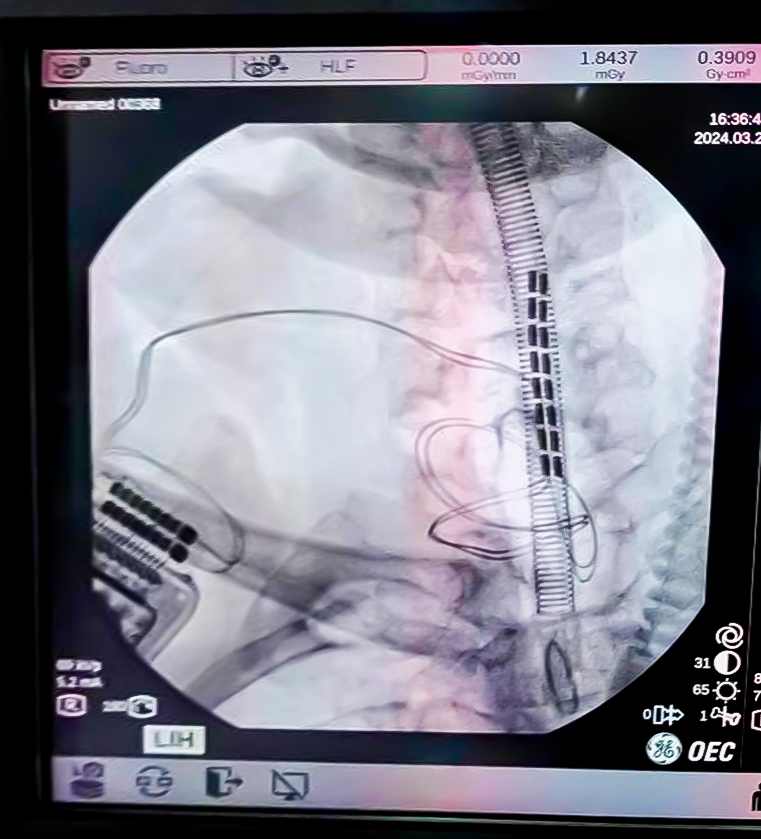

完善术前检查后,在神经外科王文华主任的指导下陈龙主任医师和陆维主治医师为余先生行脊髓神经刺激器置入术。

图片

▲术中透视电极植入位置精准